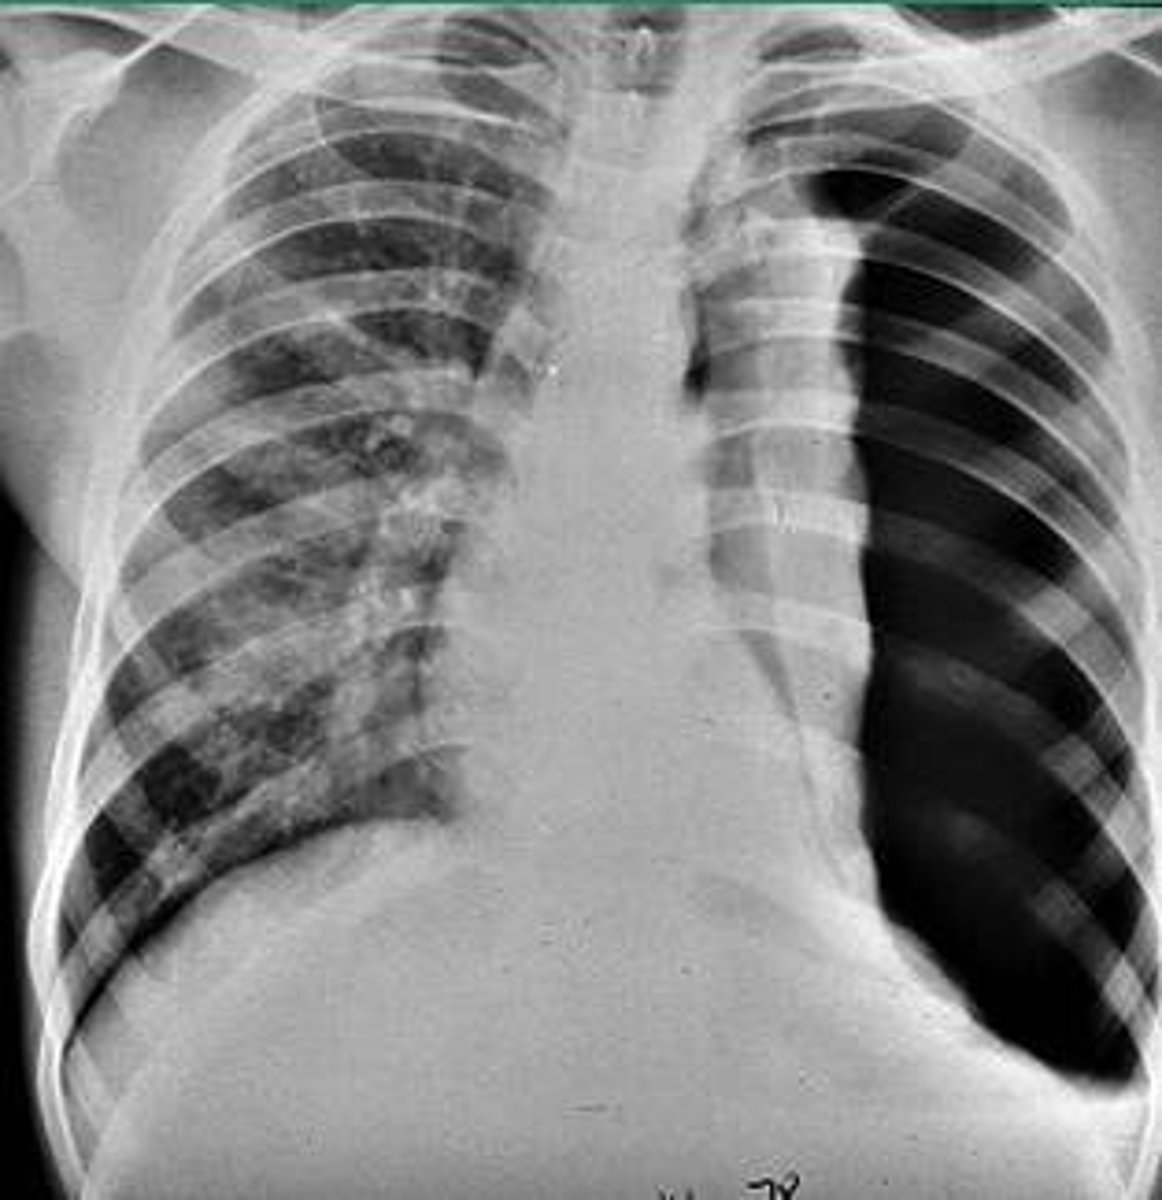

pneumothorax

air in the pleural cavity caused by a puncture of the lung or chest wall

COPD (chronic obstructive pulmonary disease)

A group of lung diseases that block airflow and make it difficult to breathe.

chronic bronchitis

a condition in which the bronchi in the lungs are constantly swollen and clogged with mucus

emphysema

A serious disease that destroys lung tissue and causes breathing difficulties.